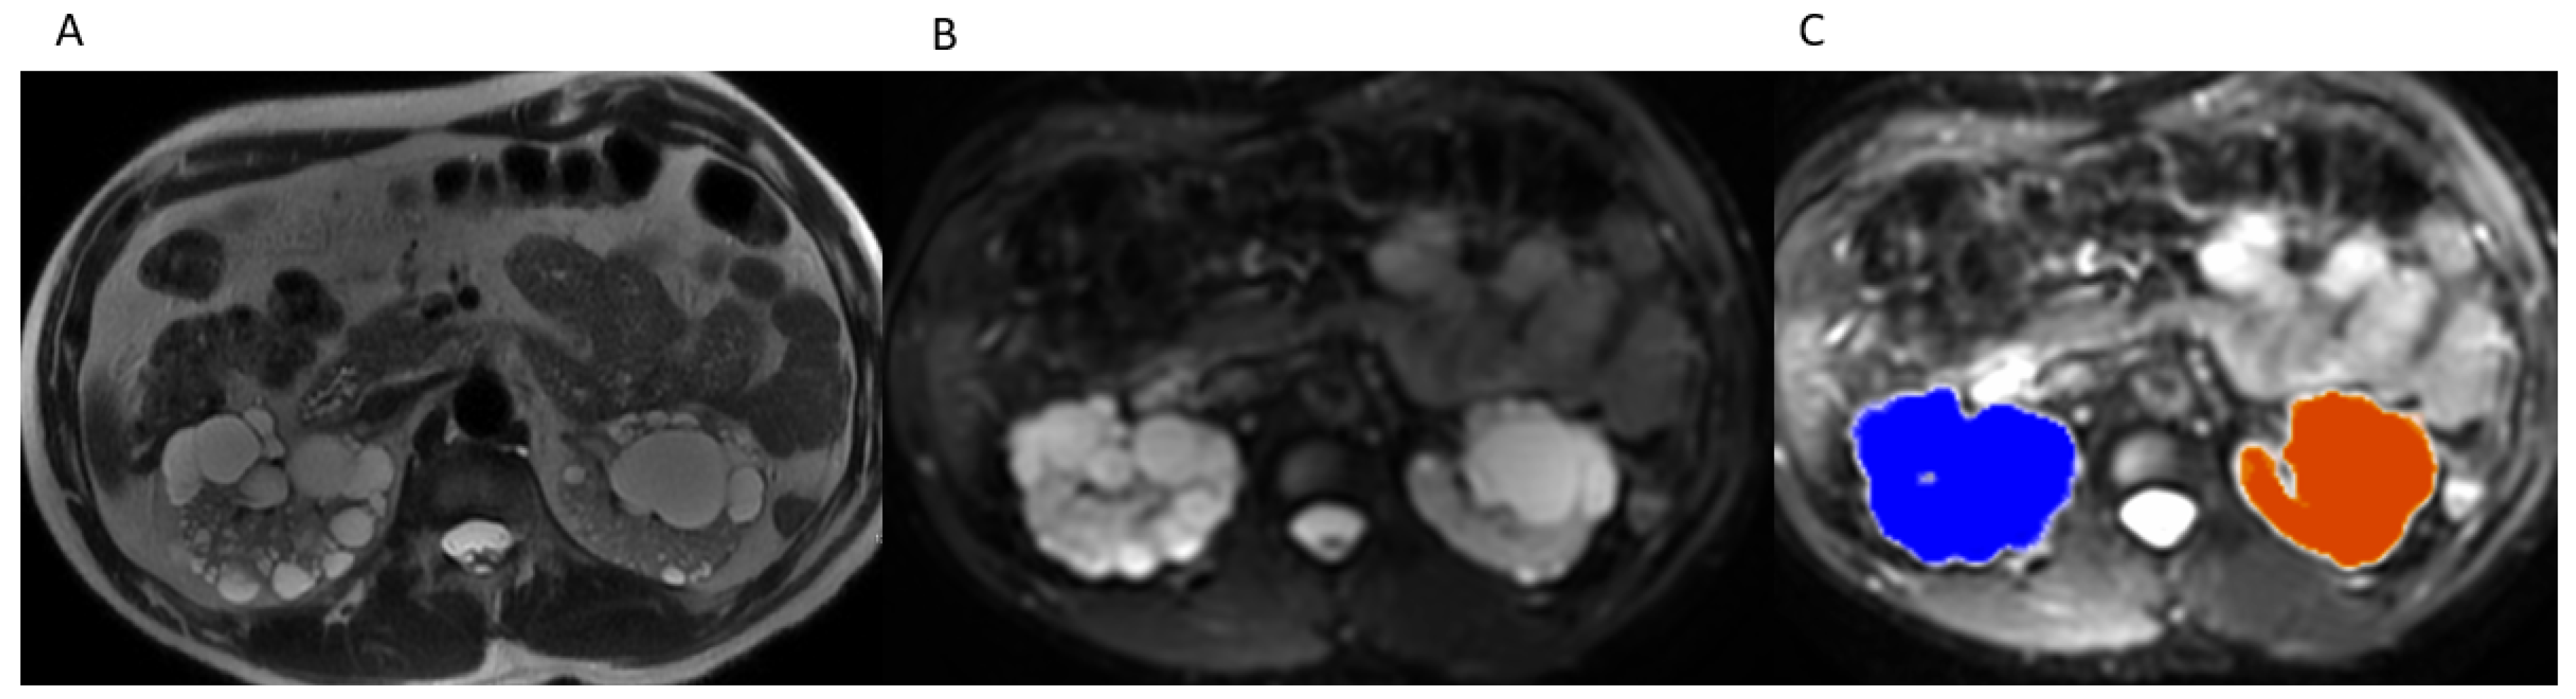

2.3. TKV Calculation